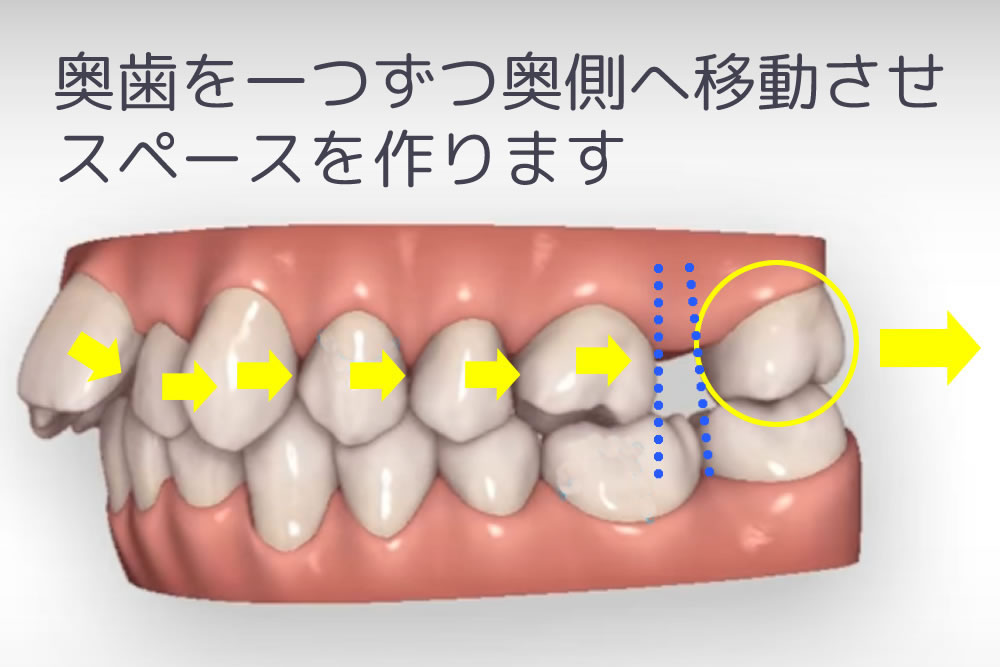

歯を少しずつ奥に移動する遠心移動法

歯列を乱している歯が歯列に収まるように、奥歯をさらに奥に移動させてスペースを作る遠心移動法で十分なスペースを確保します。その際に使用する装置が、ミニインプラントを使用したインプラントアンカー矯正や、マウスピース矯正に代表されるインビザラインなどになります。この方法を実施する事で、健康な歯を残しながら歯列矯正が可能になります。